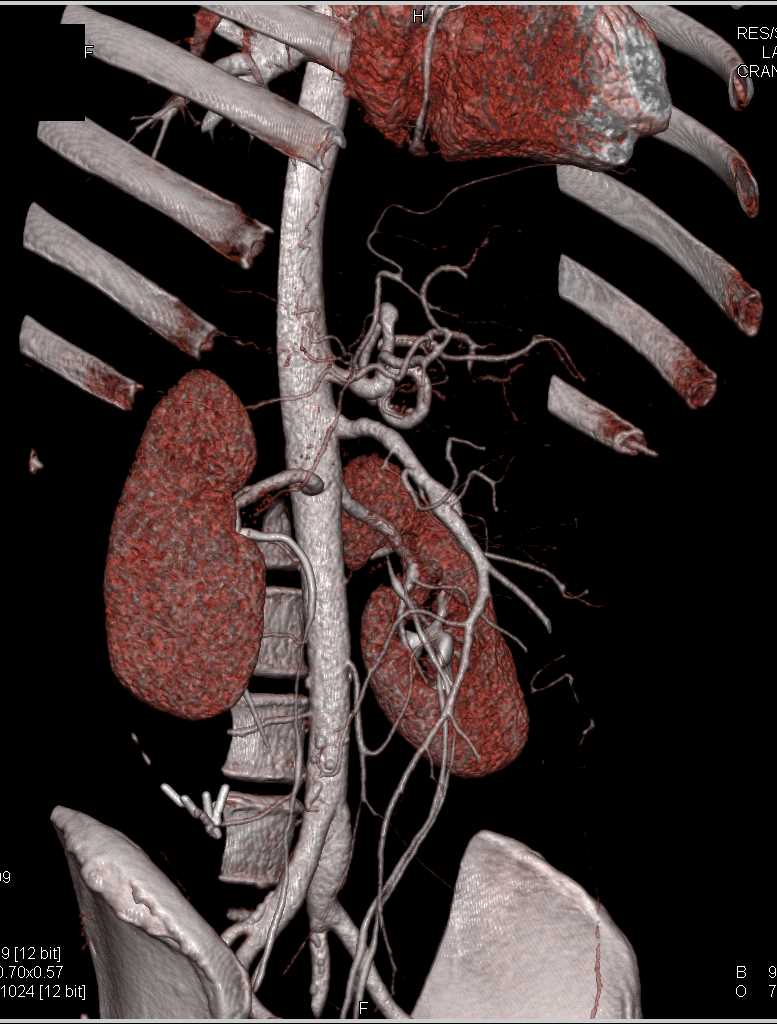

SMA Stenosis